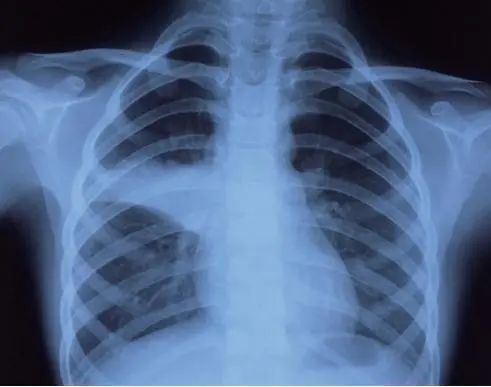

肺炎支原体肺炎的肺部体征及肺部影像学特点呈多样性改变,婴儿期可有湿性啰音,有时可呈梗阻性肺气肿体征。年长儿往往缺乏显著的胸部体征。肺炎支原体肺炎X线表现多样,有时仅为肺门阴影增重,多数呈不整齐云雾状肺浸润影,少数为大叶性实变影,可见肺不张,肺部阴影可呈游走性。CT大多数表现为磨玻璃样改变及肺间质性改变,体征轻微而胸片阴影显著,是本病特征之一。重症支原体肺炎时,可出现大叶性实变、坏死性肺炎、胸腔积液等。从目前住院患儿看,今年肺炎支原体感染所导致的大叶性肺炎明显高于往年。